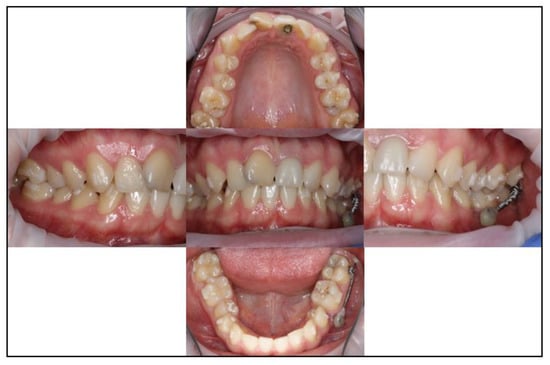

3.1. Case No. 1

3.2. Case No. 2